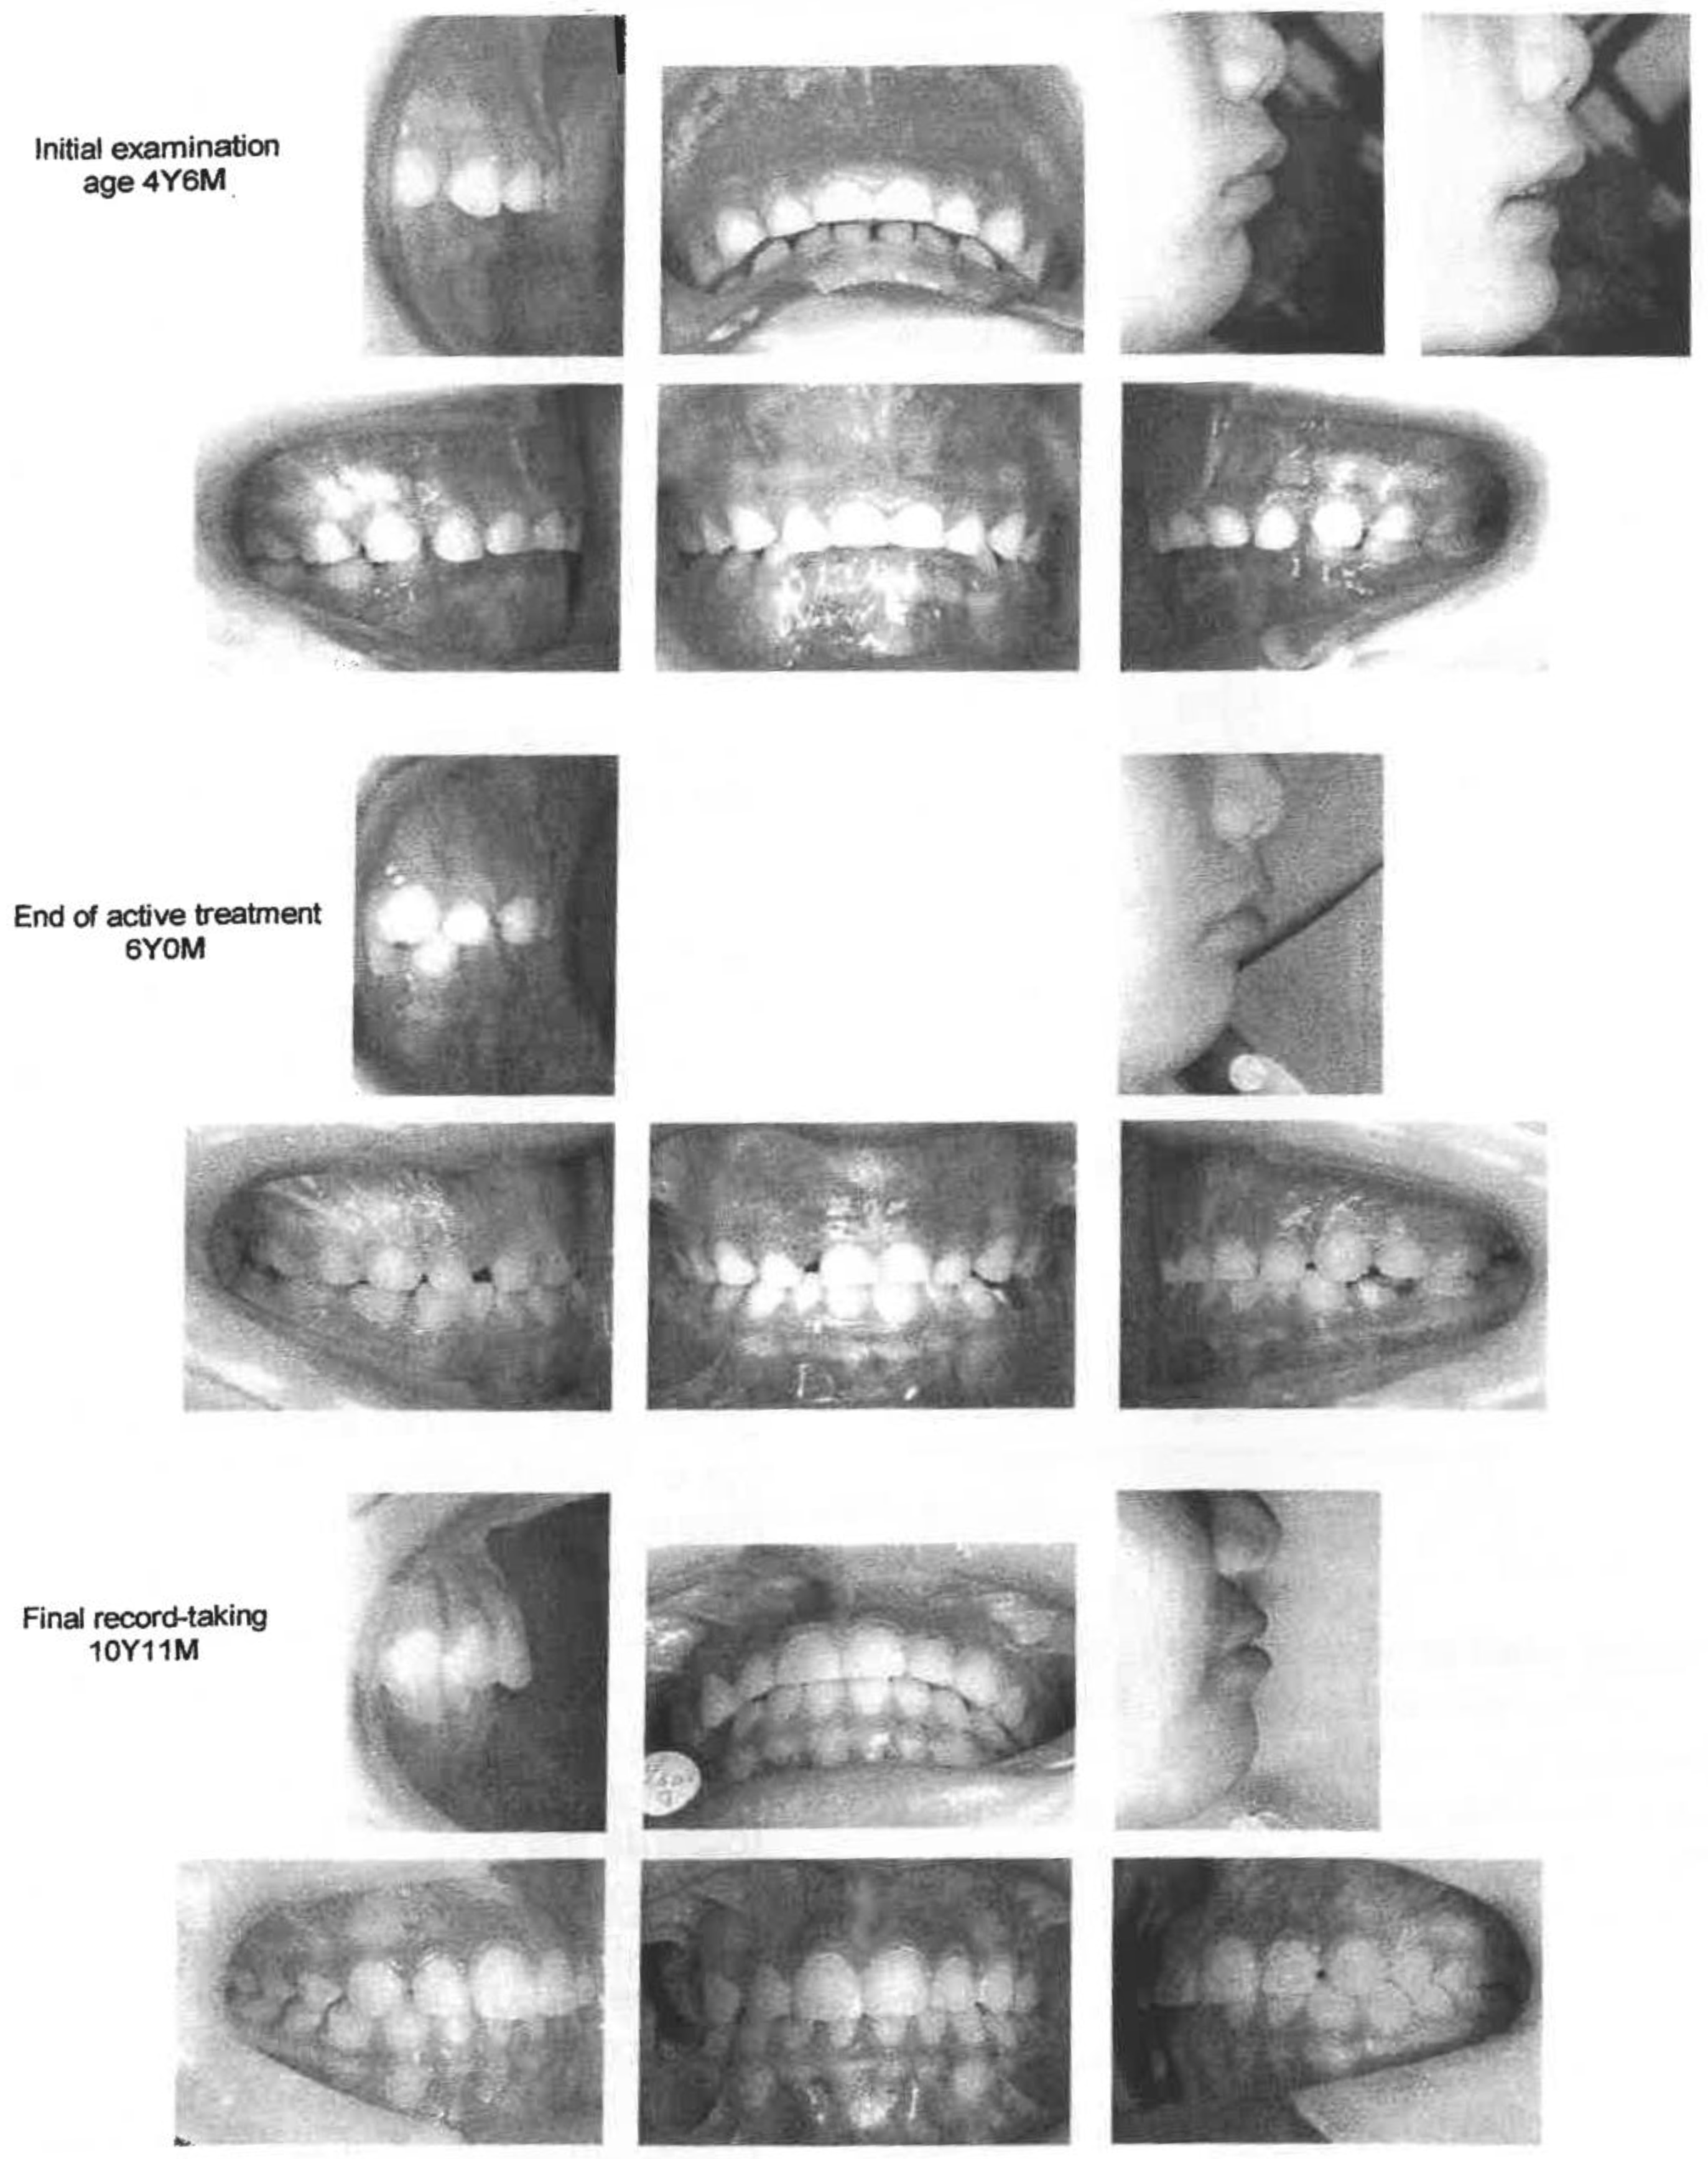

Figure 2. Case 1 - Intraoral photographs.

In the frontal view, the face was almost symmetrical, and the habit of sucking and biting the lower lip was noted. In profile, the upper lip was protrusive, while the chin was retruded with mentalis strain upon lip closure. Her intraoral findings included a marked overjet, a deep bite with the lower incisors biting into the palata, and labially tipped upper deciduous incisors. Her occlusal relationship was of mesial step type with 8.5mm of overjet and 4.0mm of overbite. There was no midline deviation. Cephalometric analysis revealed labial tipping of the upper deciduous central incisors, mandibular retrognathism and low mandibular angle (Figure 2).

The case is near the completion of the permanent dentition. Molar relationship is now Angle Class I with 2.0mm of overjet and 1.5mm of overbite. Cephalometric comparison at the start and prior to the end of F.A. treatment revealed changes in the SNB angle from 75.8° to 75.7°, theANB angle from 7.0° to 6.6°, Mand. pl. from 90.2° (to LA) to 99.4° (to L1), and UA-SN from 107.9° to 94.7°.

The elimination of lip sucking and lip biting and stimulation of forward mandibular growth in Phase I resulted in favorablejaw and incisor relationships and a good forward growth of the mandible. The lip protrusion and soft tissue profile were improved at the same time. The patient and parents were satisfied with the facial improvement, and the parents were pleased with the child's improved self-image (Figure 4 and Figure 5) (Table 2).